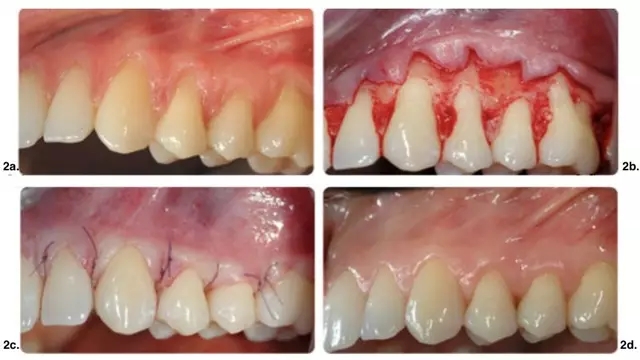

皮瓣設計無垂直切口治療多顆牙牙齦萎縮。實驗組手術(shù)及術(shù)后效果如圖 1 所示,CTG(涉及至少 2 個相鄰牙的牙齦萎縮)應用在有張力區(qū)域。對照組僅使用 CAF(圖 2)。

圖 2. 單獨應用 CAF 手術(shù)示意圖。